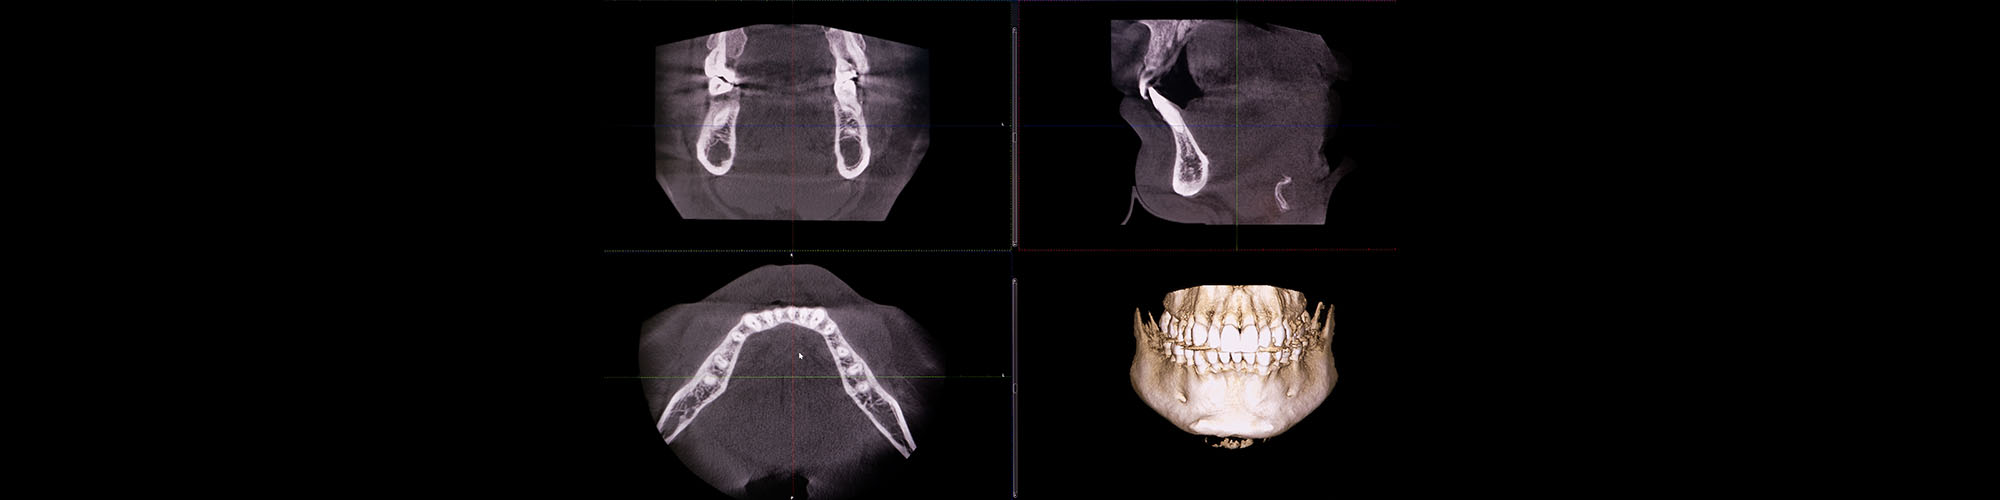

Für die Diagnostik und Behandlungsplanung steht uns in unserer Praxis ein digitaler Volumentomograph der neuesten Generation zur Verfügung, der folgende Vorteile für Ihre Patienten bietet:

• Hervorragende 3-D-Bilder mit den exakten Darstellungen des Knochenangebotes, der Ausdehnung der Kiefer- und Nasenhöhle, der Lage des Nervus alveolaris inferior etc.